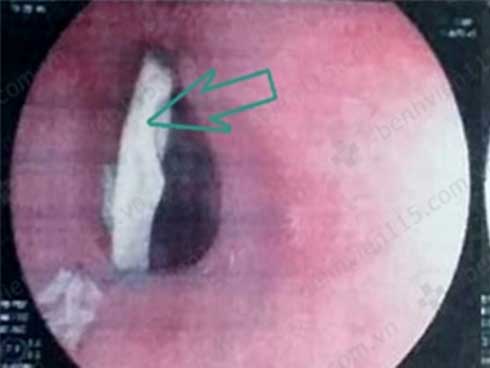

Kết quả nội soi thực quản cho thấy mảnh xương gà (trái) và lỗ thủng thực quản sau khi gắp xương gà ra ngoài (phải). Ảnh: BV CUNG CẤP

Kết quả nội soi thực quản cho thấy xương gà dài khoảng 40 mm nằm ở 1/3 giữa thực quản. Điều đáng nói xương gà nằm ngang, hai đầu cắm sâu vào thành thực quản nên nhiều khả năng gây thủng thành thực quản.

Sau khi lấy xương gà ra ngoài, các bác sĩ (BS) phát hiện thành sau phải thực quản giữa có một vết thủng khoảng 3 mm. Kết quả chụp CT scan cho thấy ông H. bị viêm trung thất .